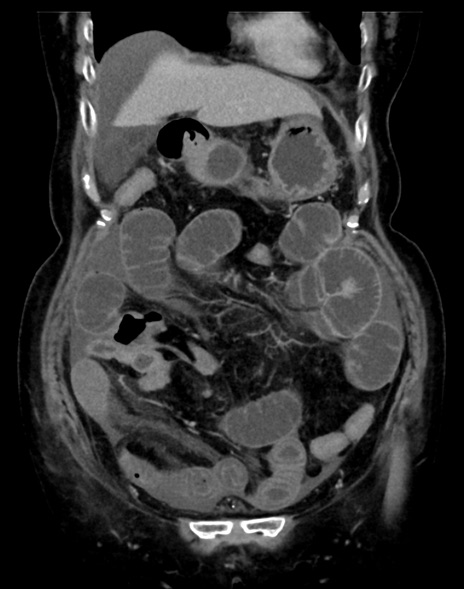

症例13 CT(冠状断像)1日半後